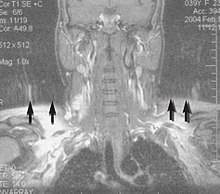

MRI is the investigative tool of choice for neurological cancers over CT, as it offers better visualization of the posterior cranial fossa, containing the brainstem and the cerebellum. The contrast provided between grey and white matter makes MRI the best choice for many conditions of the central nervous system, including demyelinating diseases, dementia, cerebrovascular disease, infectious diseases, Alzheimer's disease and epilepsy.[22][23][24] Since many images are taken milliseconds apart, it shows how the brain responds to different stimuli, enabling researchers to study both the functional and structural brain abnormalities in psychological disorders.[25] MRI also is used in guided stereotactic surgery and radiosurgery for treatment of intracranial tumors, arteriovenous malformations, and other surgically treatable conditions using a device known as the N-localizer.[26][27][28] New Artificial intelligence in healthcare tools have demonstrated higher image quality and morphometric analysis in neuroimaging with the application of a denoising system.[29]

Magnetic resonance angiography (MRA) generates pictures of the arteries to evaluate them for stenosis (abnormal narrowing) or aneurysms (vessel wall dilatations, at risk of rupture). MRA is often used to evaluate the arteries of the neck and brain, the thoracic and abdominal aorta, the renal arteries, and the legs (called a "run-off"). A variety of techniques can be used to generate the pictures, such as administration of a paramagnetic contrast agent (gadolinium) or using a technique known as "flow-related enhancement" (e.g., 2D and 3D time-of-flight sequences), where most of the signal on an image is due to blood that recently moved into that plane (see also FLASH MRI).[39]